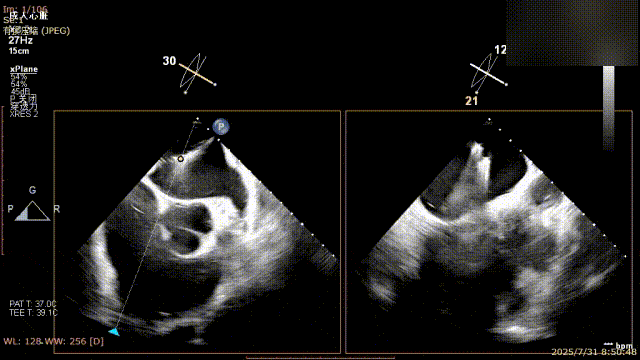

术前完善经食管超声评估,提示该患者双房大,二尖瓣重度反流4+伴后叶脱垂、后叶部分腱索断裂。根据评估结果,心脏大血管外科王安彪主任团队制定了周密的手术方案:植入一枚夹合器,钳夹P1区反流最大处,尽可能夹持全部后叶脱垂瓣叶组织,后续根据术中实时残余分流和跨瓣压差等指标,并依据实时超声监测调整治疗策略。

三维评估

二尖瓣P1脱垂偏心性返流

术前影像